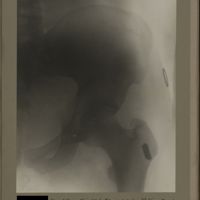

0196 - Page 84 - [Radiographie de la hanche]0196 - Page 84 - [Radiographie de la hanche]